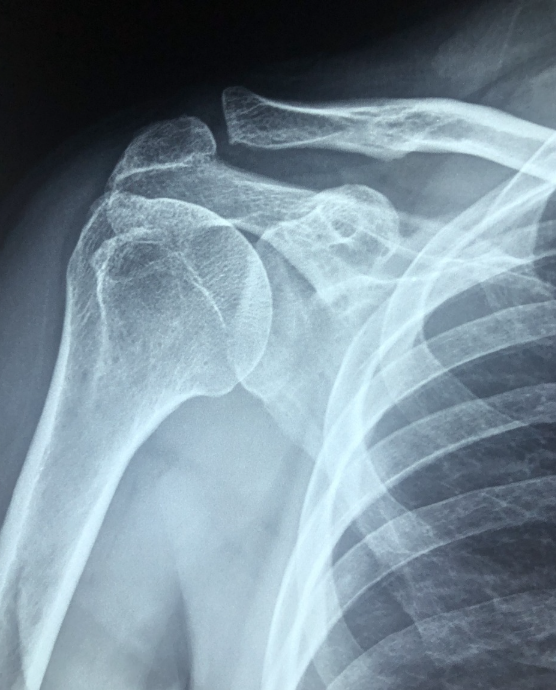

오십견, 회전근개 염증, 자세 불균형 등으로 어깨 통증을 겪고 계신가요?